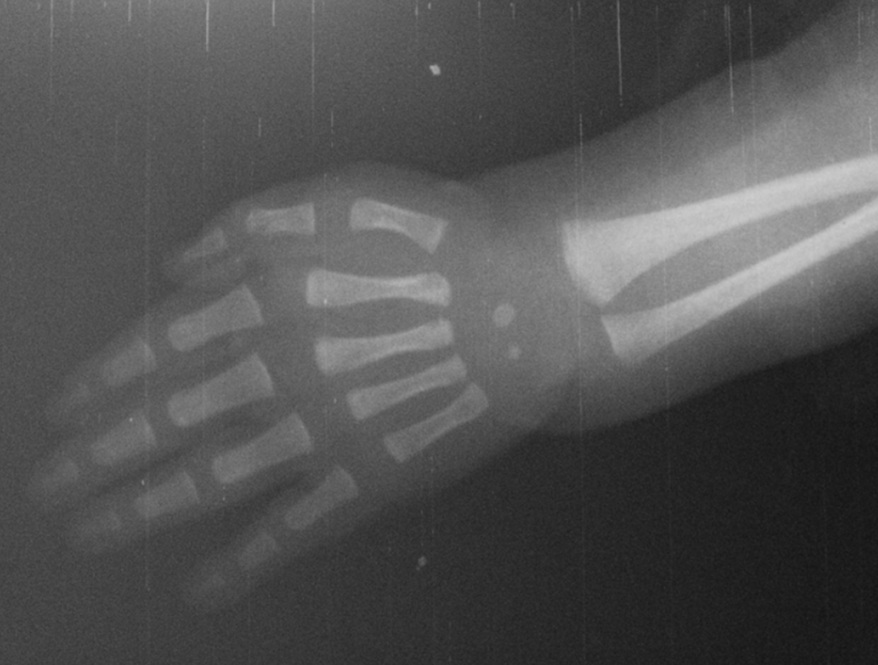

FOTO N° 2: Edad Ósea discordante con la edad cronológica. Tomado a la edad de 4 días de vida, se observa osificación carpiana como si fuera un lactante de 3 meses de edad.

En el Caso N° 1, corresponde a genitales ambiguos, clasificación Prader en estadio V, debemos resaltar que la perplejidad de los familiares ante este caso y la sensibilidad de los profesionales de la salud es lo que lleva al diagnóstico temprano. Sin embargo, se puede notar que la paciente en sus cortos 4 días de vida, presentaba hiponatremia e hiperpotasemia no sintomáticas. El nivel sérico de 17 hidroxiprogesterona estuvo muy elevado 191,900 ng/dL (muy por encima de 10,000 ng/dL3,9) con un valor de ACTH (corticotropina) cuatro veces su valor mayor normal; sin embargo el cortisol presentó un valor ligeramente bajo. La edad ósea discordante, cuatro días de vida cronológica contra tres meses de edad ósea, es un signo de excesos de andrógenos11. La Resonancia Magnética pélvica refleja ovarios con visualización de quistes y no testículos y por ello no secretan hormona antimulleriana. El objetivo del tratamiento es conseguir concentraciones séricas bajas de precursores suprarrenales y andrógenos o ligeramente por encima de los límites superiores para las mujeres normales. Esto no puede ser posible sin causar el síndrome de Cushing11. Con respecto a la esfera psicológica, la exposición prenatal del cerebro a altos niveles de andrógenos puede influir sobre comportamientos sexuales posteriores. Existe un aumento de la frecuencia de homosexualidad en las niñas afectadas12,13. Por ello urge la asignación precoz del sexo, que debe ser la del sexo genético/gonadal por la posibilidad de mantener la función reproductora; la corrección quirúrgica completa de los genitales externos se plantea que debe realizarse antes de los 18 meses de edad14.